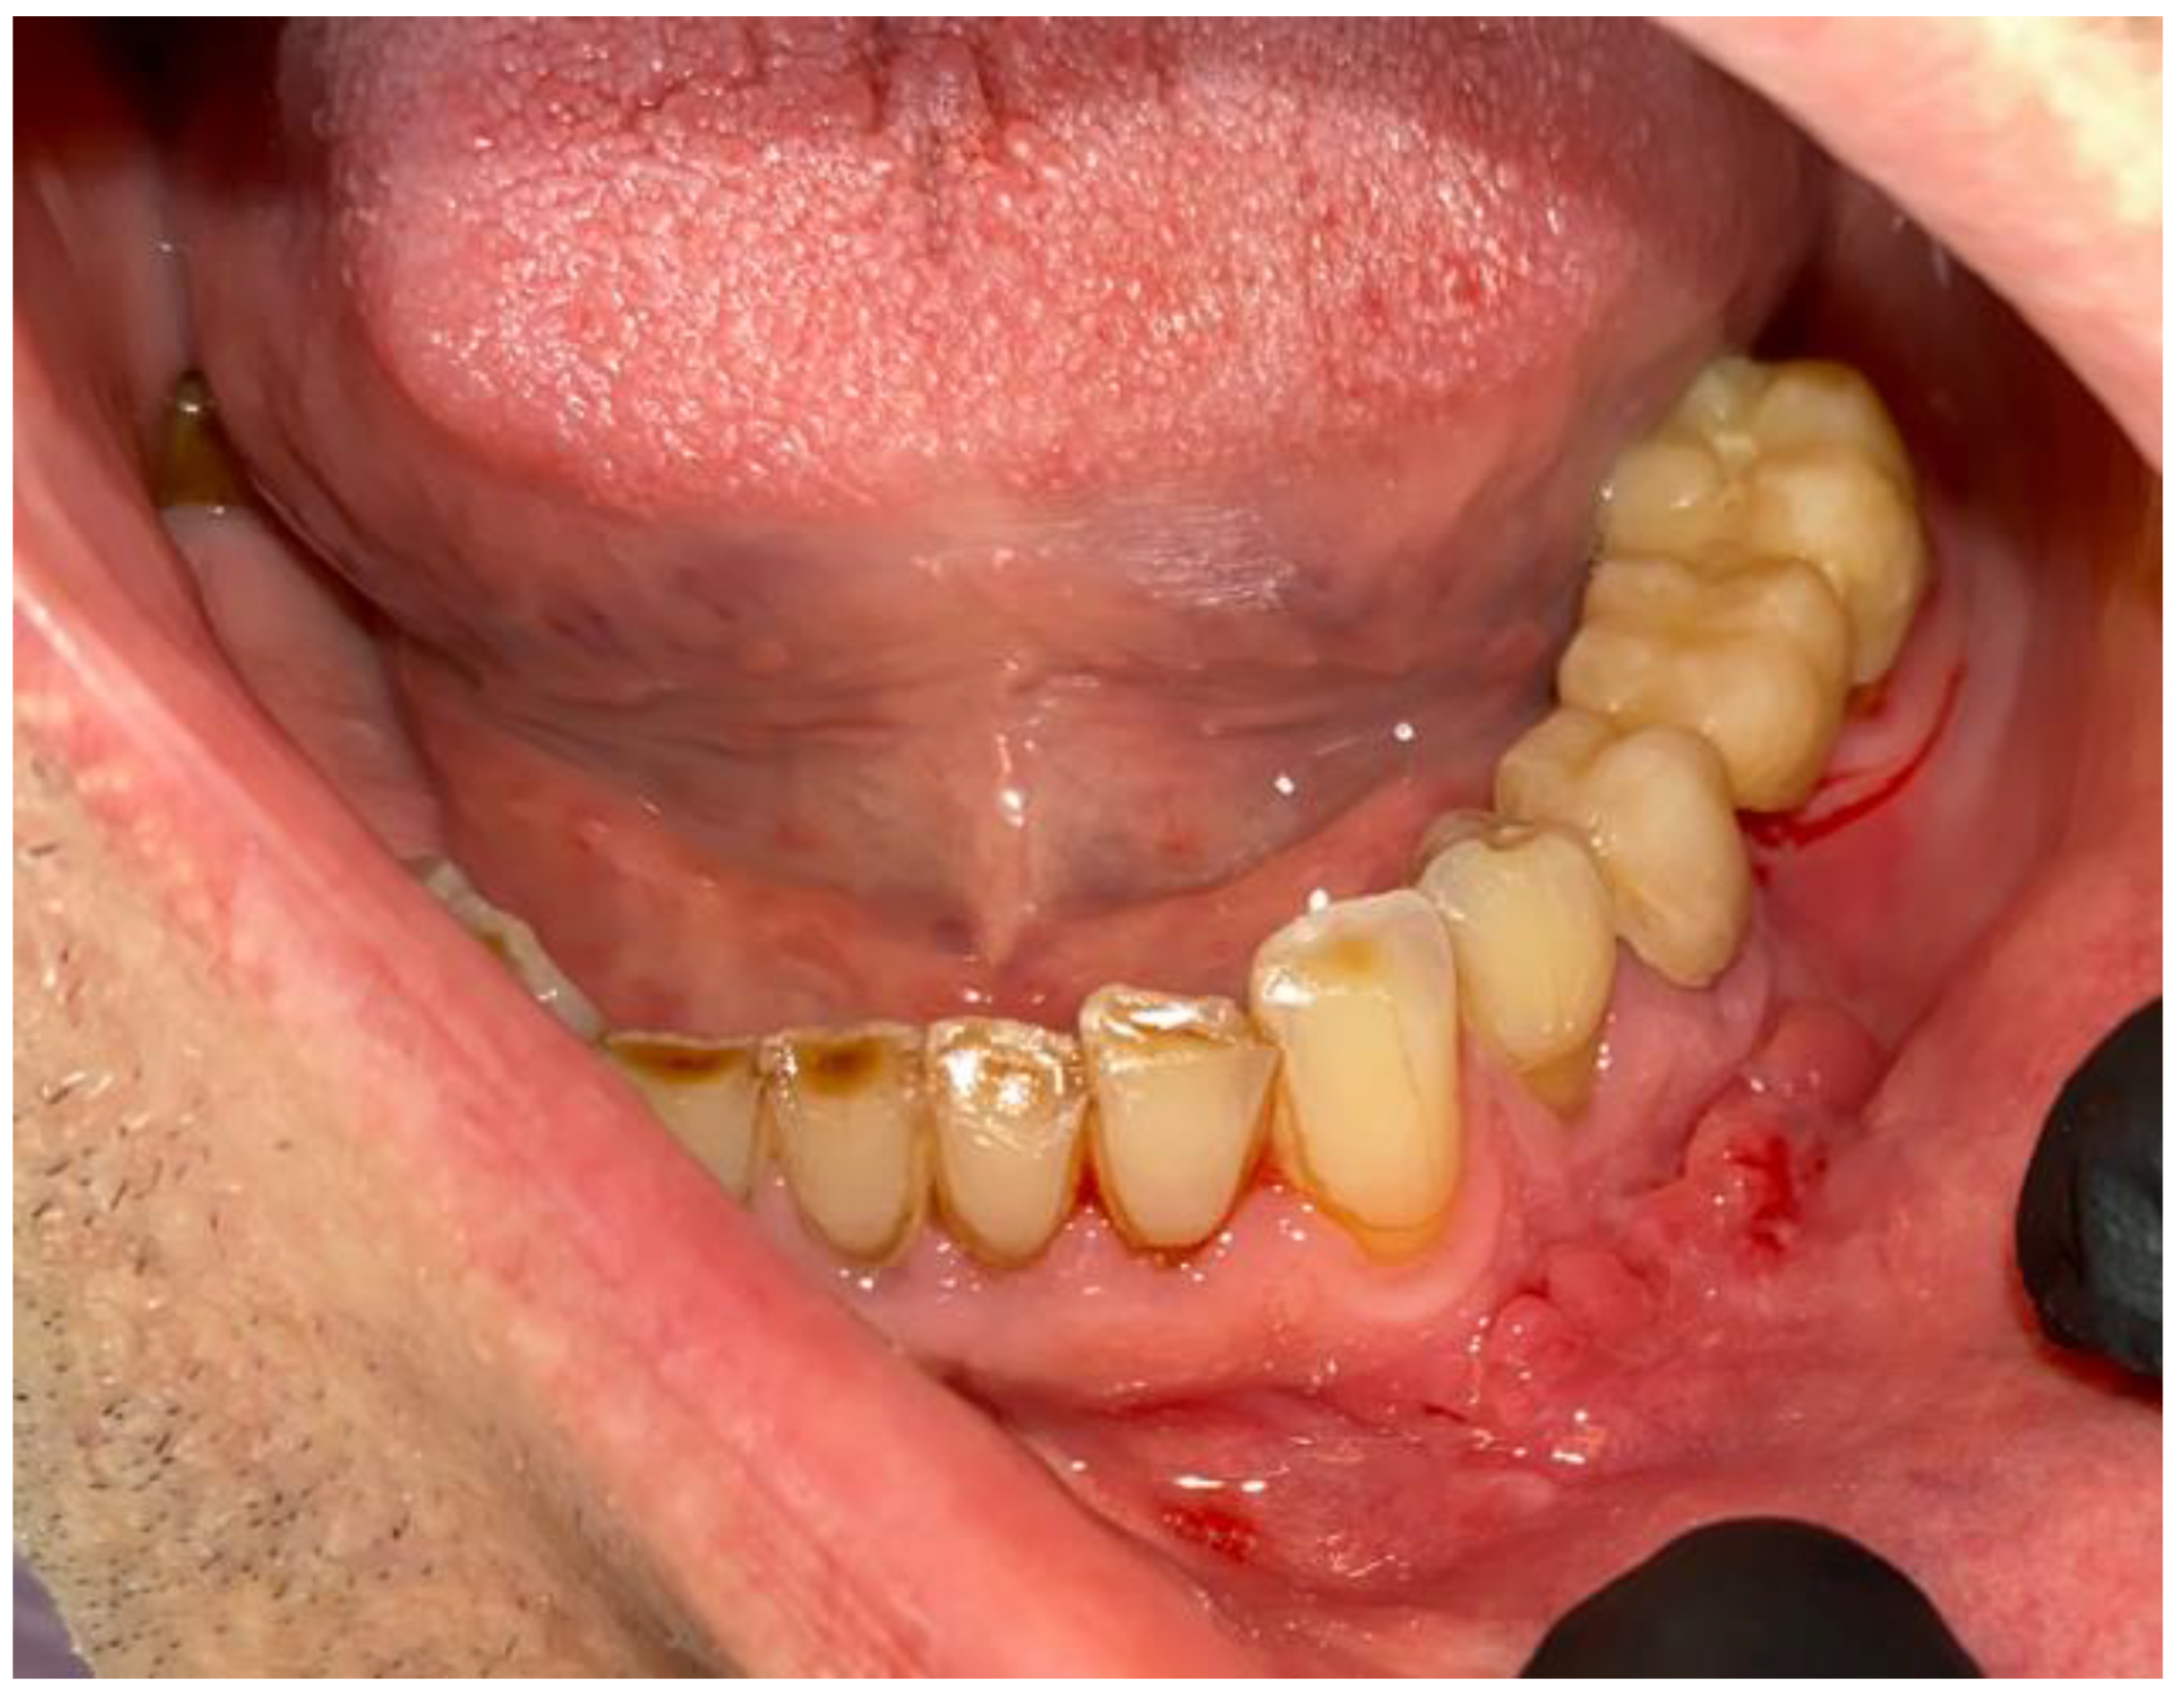

2. Case Description